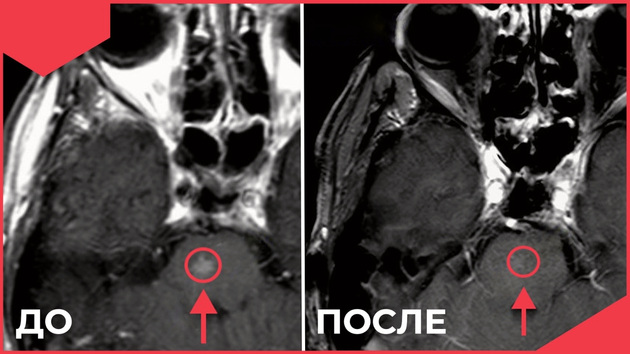

Один пример из практики. В начале 2022 года 56-летний житель Владимирской области с диагнозом “рак легкого III стадии” проходил курс базовой химиолучевой терапии в федеральном центре Москвы. Спустя 4 месяца после окончания лечения при МРТ выявлен метастаз в ствол головного мозга.

Несмотря на крайне опасный для осложнений участок головного мозга, отвечающий за проведение нервных импульсов от спинного мозга к головному, за контроль движений тела и восприятие положения в пространстве, специалистами онкодиспансера г. Владимира было принято решение провести стереотаксическую лучевую терапию на область метастаза. При контрольных МРТ через 4 и 6 месяцев метастаз не определяется, новых метастазов тоже нет. Спустя 13 месяцев пациент живет активной жизнью и продолжает лечение рака легкого.